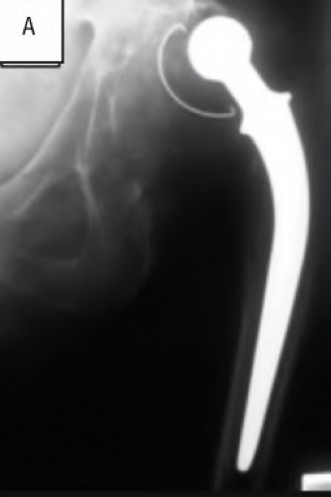

A 72-year-old male presents 2 years status post fixation of an impending pathologic right femur fracture due to metastatic renal cell carcinoma. He is minimally ambulatory due to pain. Despite radiation therapy, there has been progression of the lesion with extensive cortical bone loss, which is shown in Figure A. A proximal femoral replacement arthroplasty is performed without complications, and is demonstrated in Figure B. Which of the following is true regarding this patients post-operative course?

Deep prosthetic infection is the most common complication after hip arthroplasty performed for salvage of failed internal fixation after pathologic proximal femoral fracture secondary to malignancy.

Jacofsky et al reviewed the complications in 42 patients with a mean age of 63 who were treated with hip arthroplasty for salvage of failed treatment of a pathologic proximal femoral fracture. Multiple different constructs were used.

The most common complication was deep prosthetic infection, which occurred in nearly 10% of the patients studied. All infections occured in patients whom had previously received radiation. The mean Harris Hip score improved from 42 to 83 points post-operatively, and 41 of the 42 patients were ambulatory at follow-up. Implant survivorship free of revision for any reason at 5 years was 90%, and free of revision for aseptic failure or radiographic failure was 97%.

Figure A shows a lytic lesion of the proximal femur with an intramedullary implant. Figure B shows a proximal femoral replacement.